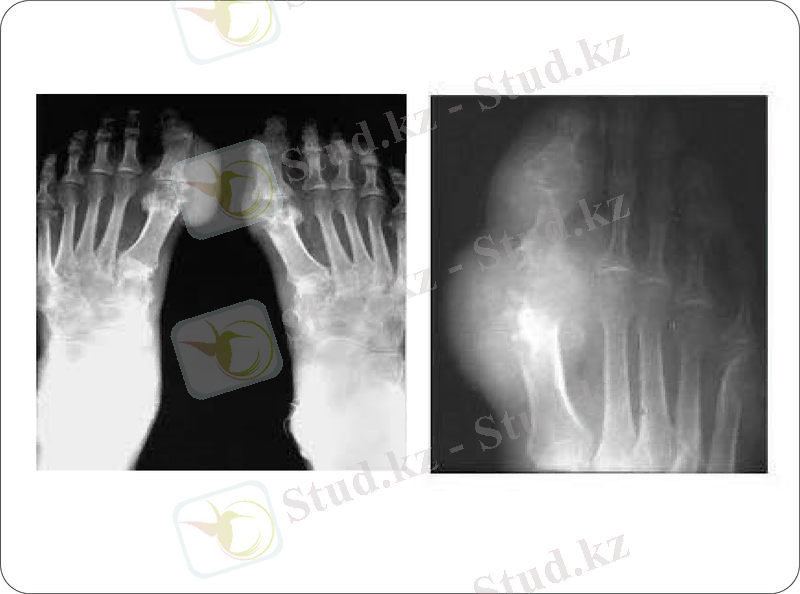

8. рентгенограммадағы буындардың симметриялы өзгерістері

9. субкортикальді қол ұшының рентгенограммадағы эрозиясы